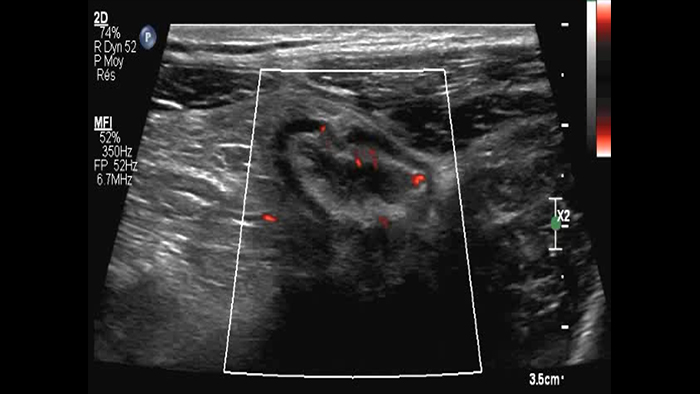

Ces images précises des lésions des couches pariétales forment la base de l’interprétation des changements induits par l’inflammation des parois intestinales et par conséquent de la différenciation entre la maladie de Crohn et la rectocolite hémorragique. L’exploration avec la technologie MFI (MicroFlow Imaging) constitue la deuxième étape. Il s’agit de reconnaître l’aspect de l’hypervascularisation induite par des épisodes inflammatoires actifs. La paroi intestinale normale semble comporter peu de microvaisseaux détectables, uniquement à l’interface de la muqueuse et de la sous-muqueuse, et dans le tissu adipeux mésentérique adjacent. Inversement, la paroi inflammatoire présente de nombreux microvaisseaux. La distinction entre les images d’artefacts de mouvement et les microvaisseaux circulants est alors un point essentiel nécessitant un ajustement parfait des paramètres de détection des micro-flux (voir les boucles, diapositive 8). La comparaison des 4 images suivantes de la maladie de Crohn met en évidence des différences claires qui devraient être interprétées comme étant représentatives des différents états inflammatoires. L’image 1 ne comporte aucun vaisseau visible, ce qui correspond probablement à une absence d’activité. L’image 2 présente quelques vaisseaux ; nous pouvons en conclure que cela correspond à une activité modérée. L’image 3 comporte un plus grand nombre de vaisseaux, signe probable d’une activité intense. L’image 4 présente encore plus de vaisseaux de type pulsatile, ce qui évoque probablement une activité très intense.

Few vessels moderate activity ?